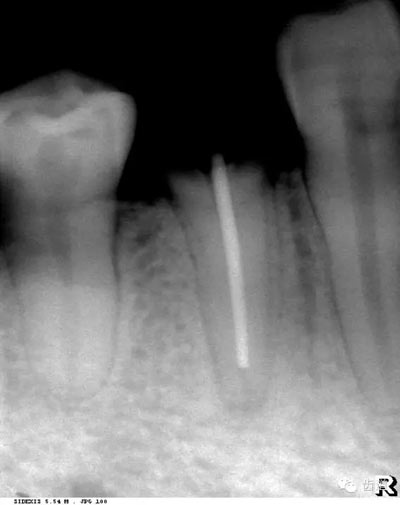

髓腔可分為冠部的髓室和根部的根管。牙髓內(nèi)含牙髓軟組織,X線片上顯示為密度低的影像。年輕人的牙、牙根未完全形成時,根尖孔粗大,牙髓腔大。隨著年齡的增長,牙本質(zhì)逐漸增多,髓腔愈狹窄,根尖逐漸變細(xì)。

是介于牙槽窩和牙骨質(zhì)之間的結(jié)締組織。牙周膜的厚度一般在0.15~0.38mm之間。X線上顯示為包繞牙根連續(xù)不斷的密度低的線條狀影像,其寬度均勻一致